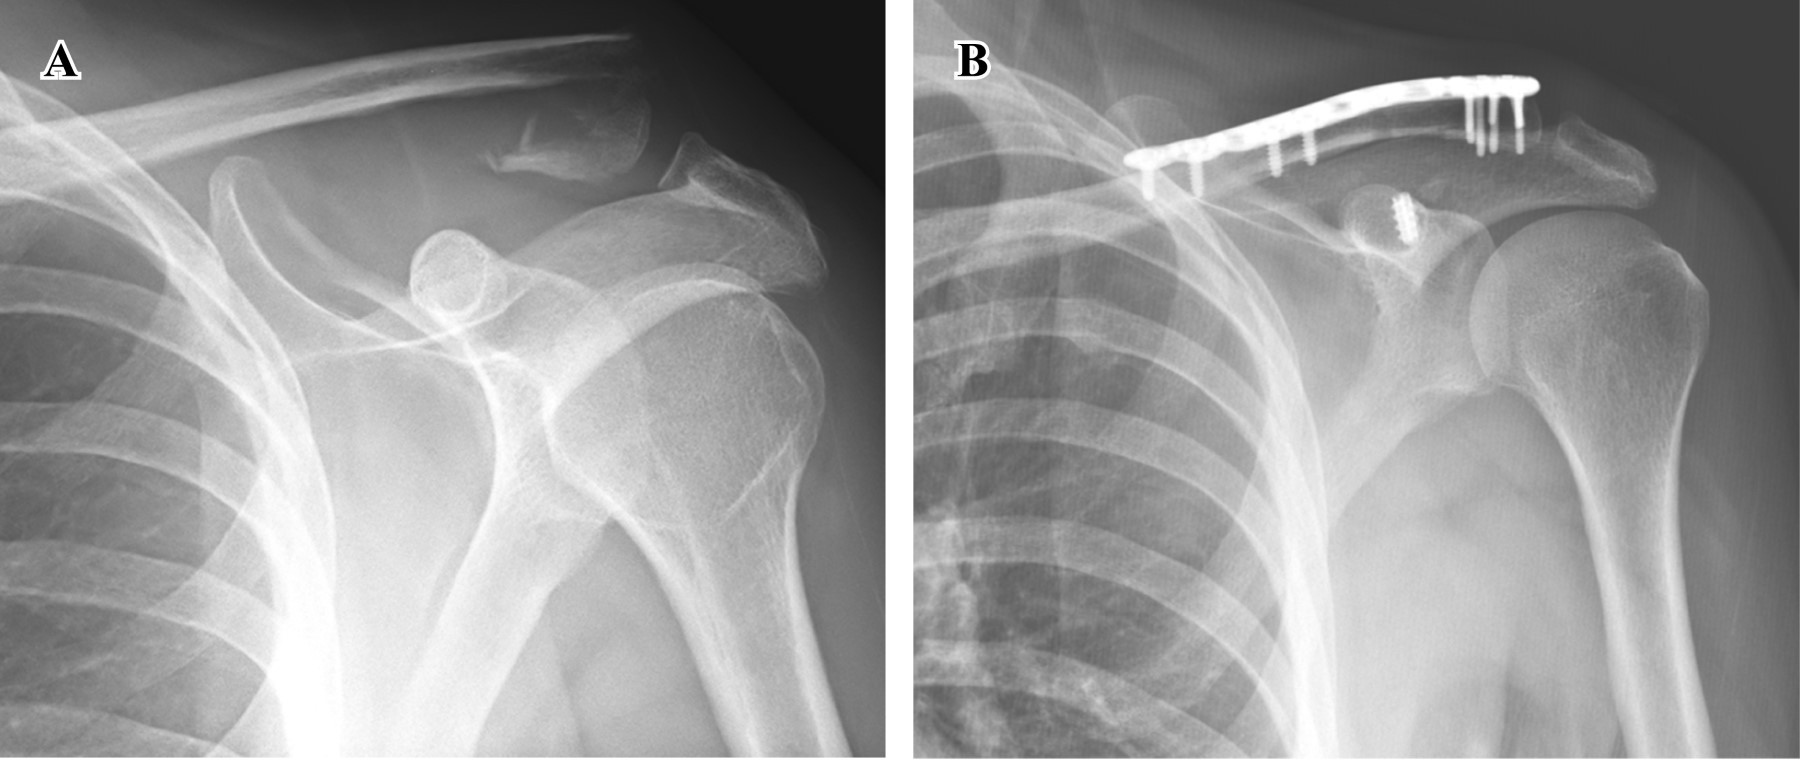

Figure 1